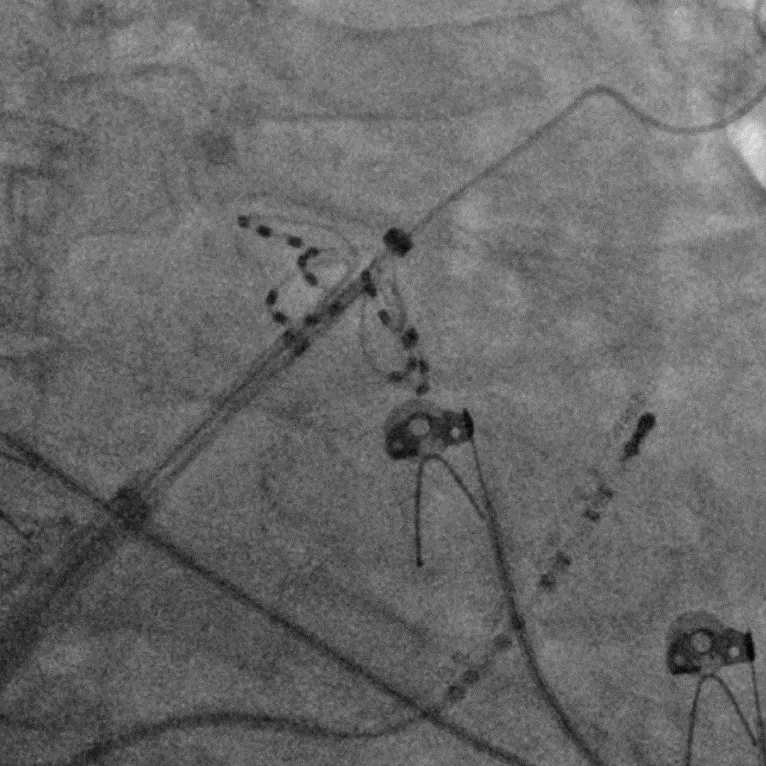

手术过程

手术在全麻下进行,消融策略涵盖双侧肺静脉、左房后壁及上腔静脉,总计消融73个位点,累计消融时间仅146秒。术中活化凝血时间(ACT)维持在250-300秒,未出现并发症。消融结束后,患者仍为房颤心律,经电复律成功转为窦性心律,手术顺利完成。

LSPV消融及前后电位对比

LIPV消融及前后电位对比

RSPV消融及前后电位对比

RIPV消融及前后电位对比

后壁消融及前后电位对比

上腔静脉消融及前后电位对比